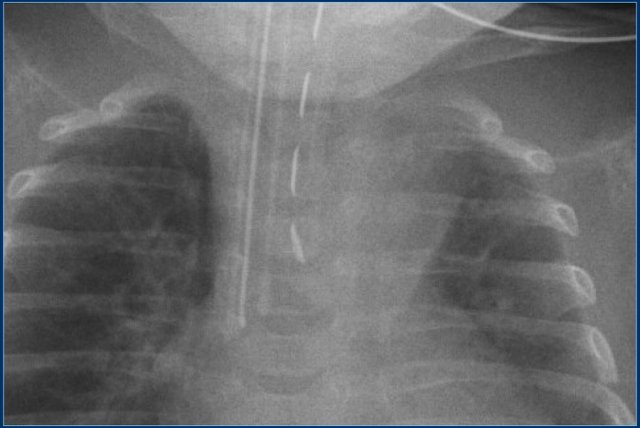

Endotracheal tube (3)

Study the image.

Then continue reading.

The findings are:

1. Endotracheal tube is positioned in the oesophagus.

2. Chest radiograph shows dilatation of the esophagus and stomach, that are filled with air (arrows).